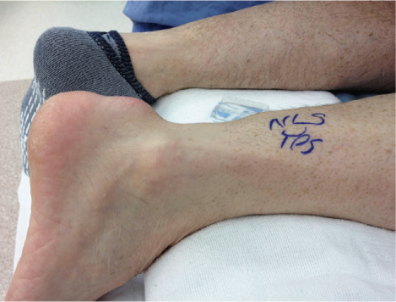

病史:详细询问受伤经过,观察患者是否存在跛行、小腿肌肉萎缩、跟腱区域肿胀或异常凹陷。

症状:疼痛非典型,患者多因踝周肿胀、行走疲劳/无力、步态不稳、爬楼/踮脚困难就诊,部分患者有持续性疼痛。

体征:沿跟腱走行触摸,感受压痛、结节或连续性中断。慢性病例断端间隙可能因瘢痕填充而不明显。